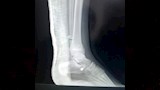

وتضمنت الإصابات كسرًا مضاعفًا في مركز النمو أسفل عظمة القصبة اليسرى، وكسرًا أسفل عظمة الشظية اليسرى، وخلعًا كاملًا في مفصل الكاحل الأيسر، وفقًا لخطورة الإصابات وتأثر مركز النمو، سارع الفريق الطبي إلى اتخاذ قرار بالتدخل العاجل منعًا لتأثير مستقبلي على حركة الطالب أو نمو العظام.

ونجح الفريق في رد الخلع بشكل فوري، أعقبه إجراء عملية تثبيت جراحي للعظام باستخدام أسلاك معدنية، وسط متابعة دقيقة لضمان إعادة العظام إلى موضعها الطبيعي وتفادي أي مضاعفات محتملة، إذ أسهمت سرعة التدخل ودقته في استقرار حالة الطالب سريعًا، قبل أن يغادر المستشفى في حالة جيدة بعد تلقيه الرعاية الطبية الكاملة.